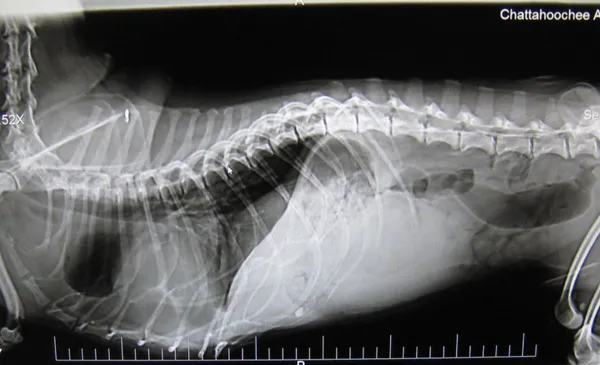

We are very proud to offer Digital Radiology in our hospital.  Digital radiology is the newest and most superior xray technology that exists.  Our digital machine is the exact same equipment used in human medicine.  The detail of our xray images is incredible, and allows for our doctors to correctly diagnose many subtle but abnormal conditions that might not be seen on plain film xrays.  Digital radiology is also a much faster process which allows the doctors to obtain high quality xrays in seconds rather than twenty to thirty minutes.  This time savings can be crucial when dealing with a critical case or an emergency.

This technology also allows the doctors to have the images reviewed by a board certified radiologist to ensure proper diagnosis.  A board certified radiologist interpretation of x-rays in the gold standard in veterinary care for image assessment. This all combines to provide our patients with the best possible radiographs and the most accurate diagnosis.